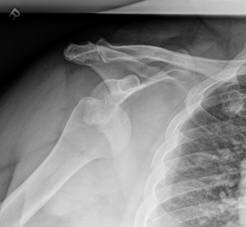

Fractures Complicating Anterior Shoulder Dislocations in Adults

JCT Wong, BSc, WS Thirsk, MD, IP Steiner, MD